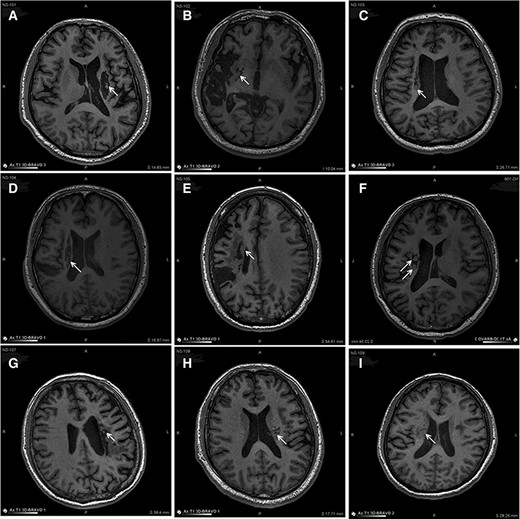

圖中顯示的是所有9名受試者(#101–109)在NSI-566移植后最新隨訪時(shí)的T1MRI圖像。箭頭指示梗塞腔位置。

(A):#101,24個(gè)月時(shí),(B)#102,12個(gè)月時(shí),(C)#103,14個(gè)月時(shí),(D) #104,9個(gè)月時(shí),(E)#105,14個(gè)月時(shí),(F)#106,24個(gè)月時(shí),(G) #107,21個(gè)月時(shí),(H) #108,12個(gè)月時(shí),(I) #109,14個(gè)月時(shí)。所有九個(gè)病例中梗塞腔內(nèi)均有新組織生長(zhǎng)。